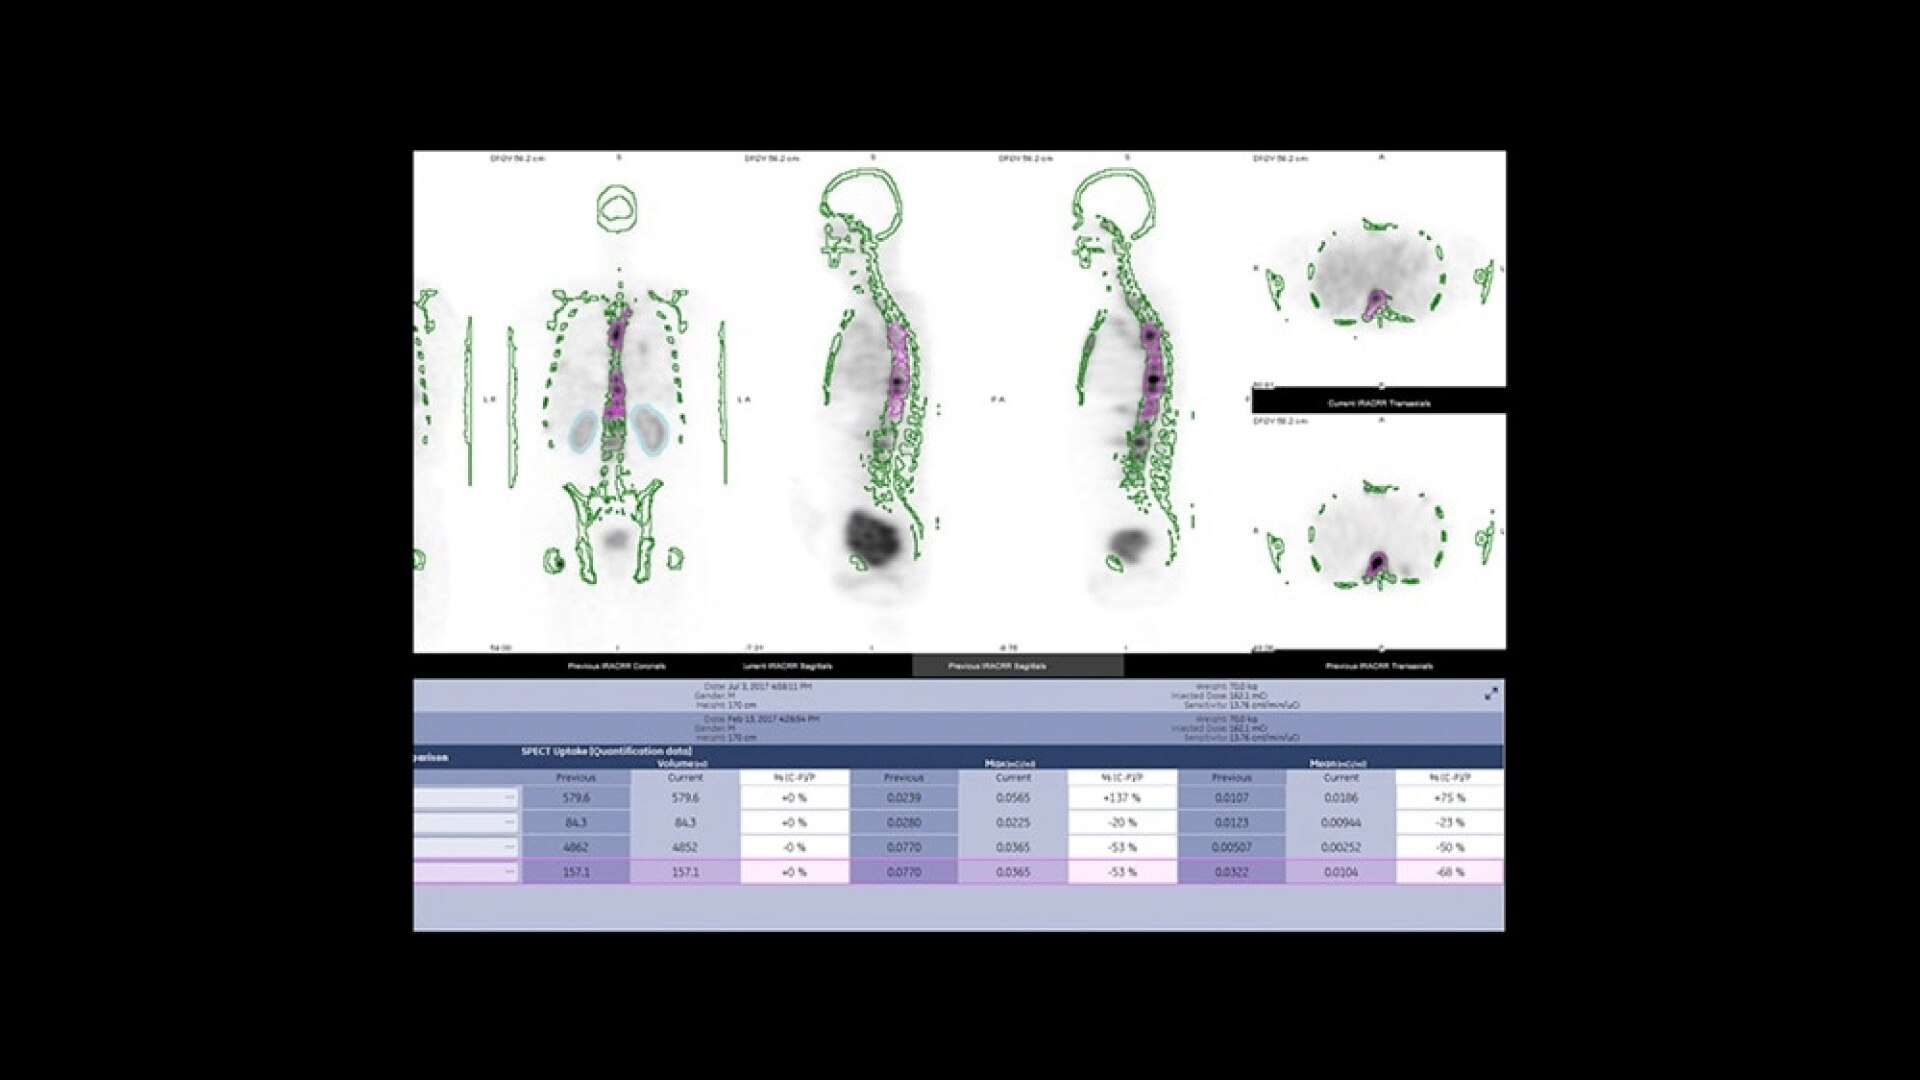

Permite realizar confirmaciones visuales sobre la marcha, lo que ayuda al equipo a tomar decisiones y colaborar en casos complejos.

Permite realizar evaluaciones para una gran variedad de zonas anatómicas, todo ello con un único dispositivo. Es posible realizar exploraciones profundas y superficiales con una conectividad de datos perfecta.